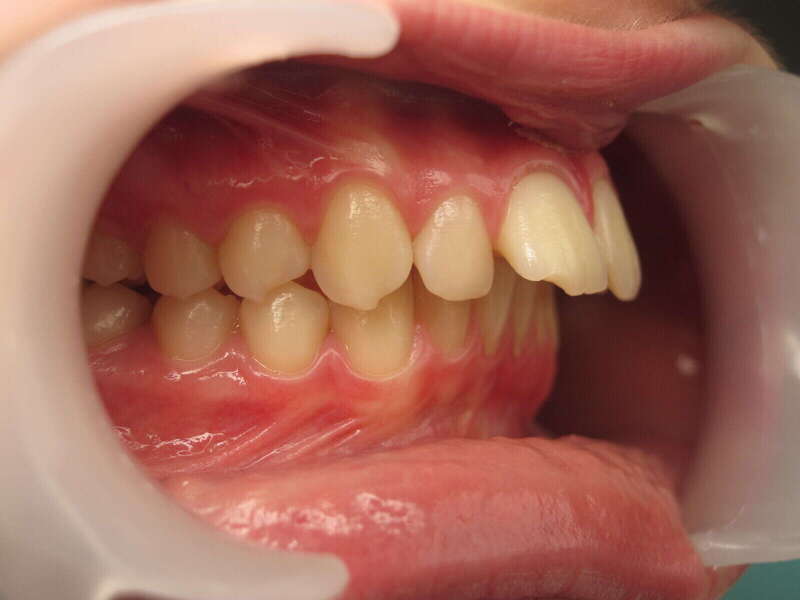

Cas n°1 traité par aligneurs - adolescent

Ce cas d’une adolescente illustre la correction d'une Classe II avec supraclusion par aligneurs. La stratégie thérapeutique a reposé sur une distalisation séquentielle de l'arcade supérieure. Ce mouvement précis a permis de reculer les dents maxillaires étape par étape pour annuler le surplomb (overjet) sans extractions.

• Correction fonctionnelle : Retour à un engrènement de Classe I stable et correction du recouvrement vertical.

• Esthétique restaurée : Harmonisation globale du sourire et du profil.

• Approche moderne : Un traitement discret, confortable et hautement prévisible.

Le résultat final montre une occlusion saine et un sourire parfaitement aligné, garantissant une santé dentaire et articulaire optimale pour l'avenir.